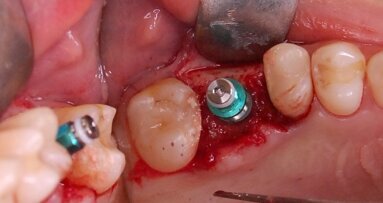

Zabieg od strony podniebienia rozpoczynano nacięciem na grzbiecie wyrostka, który przedłużano w okolicy zębów przedtrzonowych skośnie do przodu i mezjalnie (Ryc. 1a i b). Płat ustabilizowano przy pomocy szwu lejcowego, co zapewniało dobry wgląd w pole operacyjne. Etap wykonania okienka kostnego przeprowadzono przy pomocy urządzenia piezoelektrycznego (Ryc. 2a i b). Następnie odpreparowano fragment blaszki kostnej, którą po wprowadzeniu materiału kościozastępczego położono w miejscu, skąd został wycięty. Płat zreponowano bez podcinania okostnej, nie stosując membran zaporowych, po czym ranę zszyto nićmi resorbowalnymi (Ryc. 3). Analogicznie zabieg wykonano od strony przedsionka w klasyczny sposób.

Ryc. 2 a_Wytworzenie okna kostnego od strony podniebiennej, uwidaczniając nienaruszoną membranę Schneidera.

Ryc. 2 b_Wytworzenie okna kostnego od strony podniebiennej, uwidaczniając nienaruszoną membranę Schneidera.

Ryc. 3_Wprowadzenie materiału kościozastępczego oraz zreponowanie i zaszycie płata śluzówkowo-okostnowego.